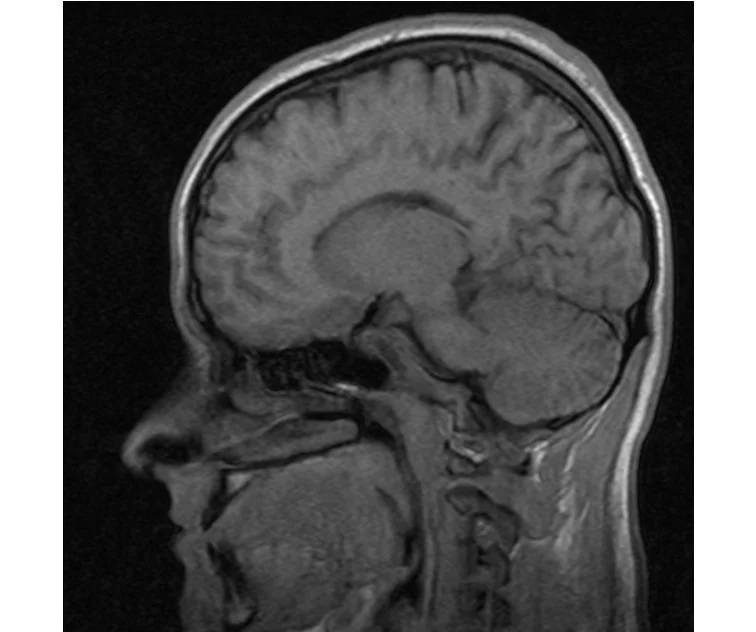

глянте на снимки томографии плиз

делал в обласной на siemense.В заключении выданом мне через 15мин.после мрт (легкая дегидрация)

Меня смутил факт выдачи заключения через 10мин(наверно они у них зарание напечатаные)я не медик.достаточно мимолётного взгляда на снимки?А вы видете на них гидроцефалию? Я лиш спросил куда идти с результатами томографии?и не хотел никого роздражать.

Я попросил взглянуть на снимки и сказать видна.ли на них гидроцефалия?или куда обратится за консультацией по этому вопросу?В мрт снимках наверно розбирается любой нервопатолог(я так предположил)

Я уже говорил, что независимо от того, есть на МРТ гидроцефалия или нет, лечиться тебе нужно только в том случае, если есть какие-либо проявления болезни, иначе на все эти анализы можешь забить... Но давай все-таки разберемся с томограммой.

Итак, с самого начала томограмма обозначала срез какого-либо органа на определенной глубине, позволяла заглянуть вовнутрь. При компьютерной томографии аппарат делает десятки срезов головного мозга в разных направлениях и из этого множества срезов он моделирует полноценное объемное изображение мозга в натуральную величину. Обрати внимание, компьютер работает не с этими миниатюрными изображениями, а с трехмерной моделью в масштабе 1:1. Эту модель вдоль и поперек анализирует суперсовременный компьютер, выполняющий миллионы операций в секунду. Только ***** может пытаться перепроверить компьютер, ведь человеку не хватит всей жизни чтобы проанализировать то, что компьютер с тобой сделал за 10 минут. Я хочу, чтобы ты это понял!

Ты разместл здесь несколько миниатюр и хочешь, чтобы врач по ним создал полноценное объемное изображение в натуральную величину, а потом осмотрел его со всех сторон и дал заключение? Но ведь это невозможно. Это просто насмешка над врачом, это издевательство над здравым смыслом. Принеси Букеру уменьшенный в 50 раз снимок зуба и спроси у него, в каком состоянии там корневые каналы. Или давай я дам тебе скрин со спутниковой карты города и попрошу тебя описать, какого цвета и какой модели запечатленная со спутника машина, какой у нее гос.номер, сколько в ней пассажиров, сколько из них мужчин и сколько женщин...